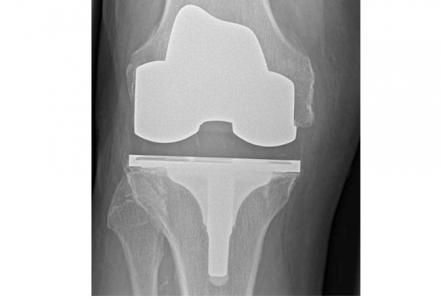

Des variations considérables en fonction des types d’arthroplasties : un remplacement de la hanche comprend principalement 2 composants (col, cavité) mais reste variable dans la manière dont ces pièces sont fixées à l'os, ainsi que dans les matériaux utilisés pour consolider la surface d'appui. Idem pour l’arthroplastie du genou, l’arthroplastie totale va remplacer toute la surface articulaire du patient, tandis qu'une prothèse de genou unicondylienne ne remplace que la partie endommagée du genou. Bref, les variations sont considérables en matière d’arthroplasties de la hanche et du genou, cependant ces facteurs ont bien été pris en compte dans l’analyse.

Arthroplasties du genou : L’analyse a porté au total sur les données de 299.221 patients, suivis pendant au moins 15 ans, 7.714 patients ayant subi une arthroplastie du genou unicondylienne ou partielle suivis pendant au moins 15 ans également, 88.532 et 3.935 (respectivement) sur 20 ans et 76 651 et 3 935 (respectivement) pendant au moins 25 ans.

- 93% des arthroplasties totales du genou et 77% des arthroplasties du genou unicondyliennes ont duré 15 ans et plus, 90% des arthroplasties totales du genou et 72% des arthroplasties du genou unicondyliennes, 20 ans et plus, 82% et 70% (respectivement) 25 ans et plus.